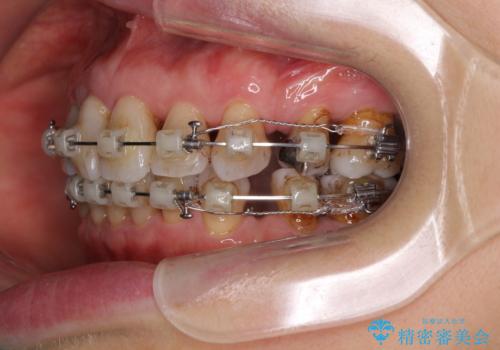

- 矯正装置

- クリアブラケット

- 突出した口元を引っ込めることを希望して来院された患者様です。

上下左右第一小臼歯4本を抜歯して、口元を改善するワイヤー矯正を行うこととしました。